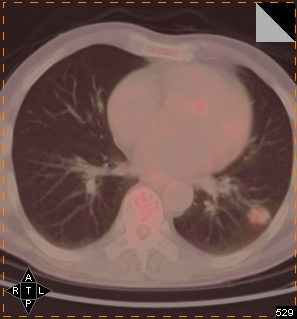

肺癌

患者,男性,65岁

间断性发热10余天。2010-09-18于当地医院行肺部CT检查:左下肺小结节影

抗炎治疗1月余,期间于2010-09-26复查胸部CT:左下肺结节影,较09-18病变有所缩小

2010-10-11复查胸部CT:左下肺结节影,较2010-09-26相仿